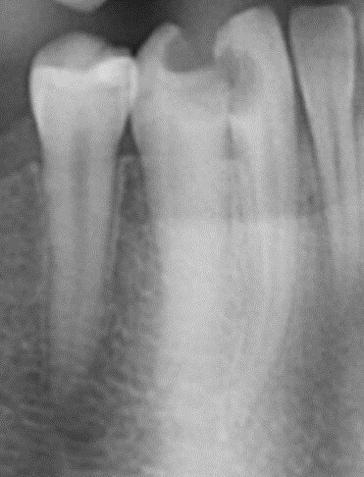

A 27-year- old male was admitted to the Endodontic Department of [Redacted] Medical Center for the past three days pain in the right front region. Medical history was noncontributory. Patient gave a history of spontaneous pain lasting from a few seconds to several hours. Also, pain is caused when hot and cold liquids are used, and is felt longer and more pronounced when hot, while cold relieve pain. Clinical examination revealed a carious cavity lesion penetrating the pulp of tooth # 43 (lower right canine). Tooth was tender to percussion. No swelling or fistula intra or extra orally. A diagnosis of irreversible pulpitis was made. Careful examination of the radiograph demonstrated a long root and the possibility of more than one canal (Fig.1)

Fig.1